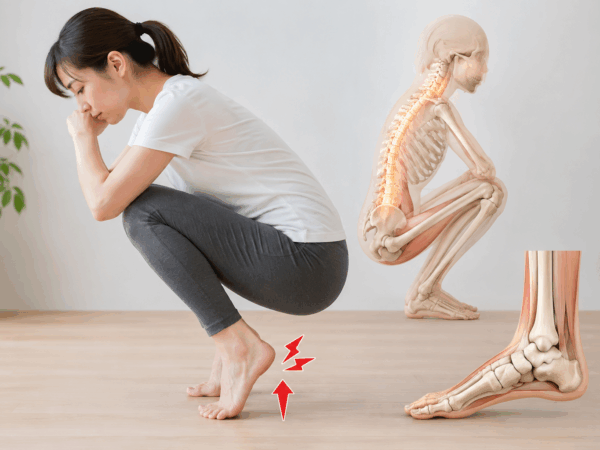

しゃがむとかかとが浮く…それ、足首だけの問題じゃないかもしれません